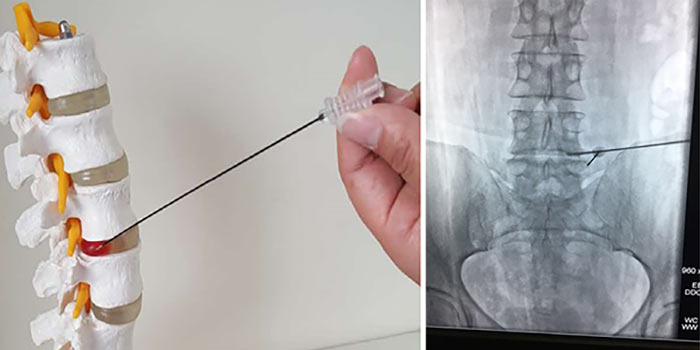

Диагноз подтверждают с помощью биопсии. Врач получает фрагмент опухолевой ткани и отправляет в лабораторию для цитологического, гистологического исследования, молекулярно-генетических анализов. Материал для биопсии может быть получен разными путями:

- Чаще всего проводят пункционную чрескожную биопсию с помощью иглы, которую вводят под контролем рентгена.

Для стабилизации позвонков и уменьшения болей может быть выполнено миниинвазивное вмешательство. В позвонок вставляют иглу и восполняют объем костной ткани специальным цементом.